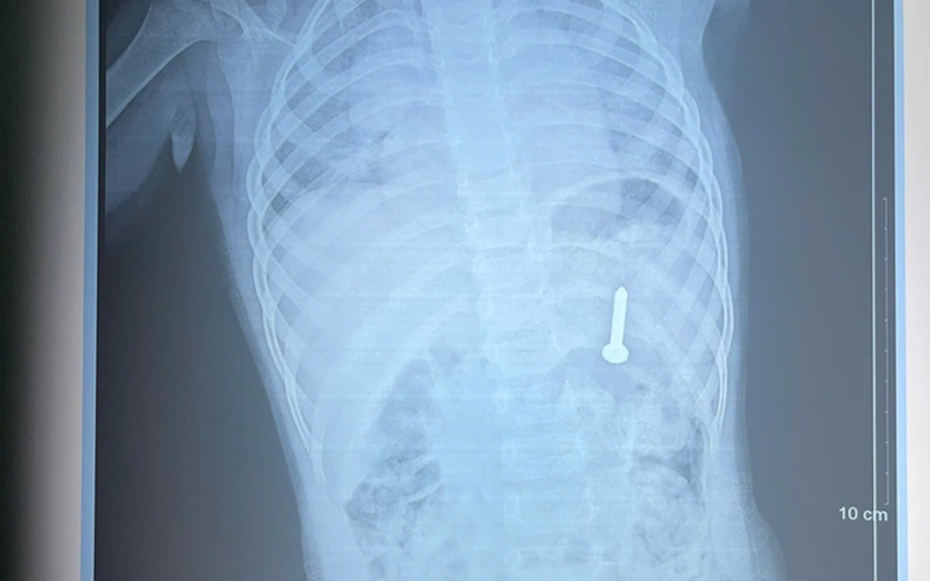

Qua thăm khám và chụp X-quang, các bác sĩ xác định dị vật nằm trong dạ dày. Nếu không được xử lý kịp thời, dị vật có thể gây thủng đường tiêu hóa, xuất huyết và nhiều biến chứng nguy hiểm.